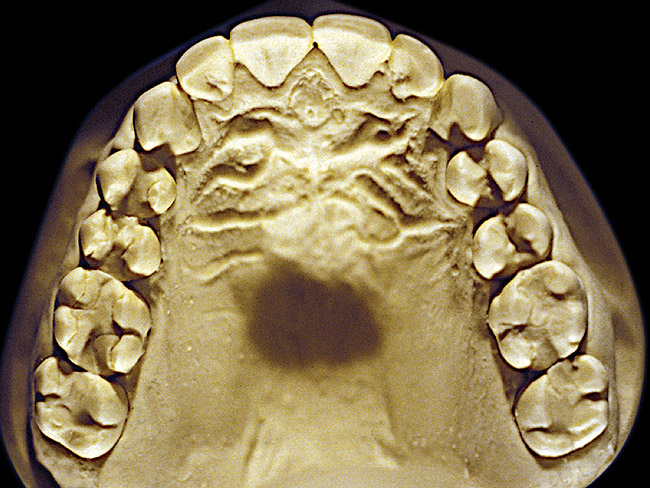

Figure 5  Moderate NCLTS from bruxism, maxillary arch.

Figure 5

The patient shown in Figure 3 and Figure 4 exhibited severe NCLTS from bruxism. Examination of the casts indicated that the NCLTS was progressively greater toward the anterior teeth. Cupping and cratering was not present because there was no secondary cause. Figure 5 and Figure 6 detail another bruxism patient, but to a lesser degree and one with cupping/cratering caused by toothpaste. The cups or craters were not caused from bruxism because the teeth could not touch the bottom of the invaginations. In both featured patients, upon hand-articulating the casts, the NCLTS facets matched up and the diagnosis of bruxism was confirmed.